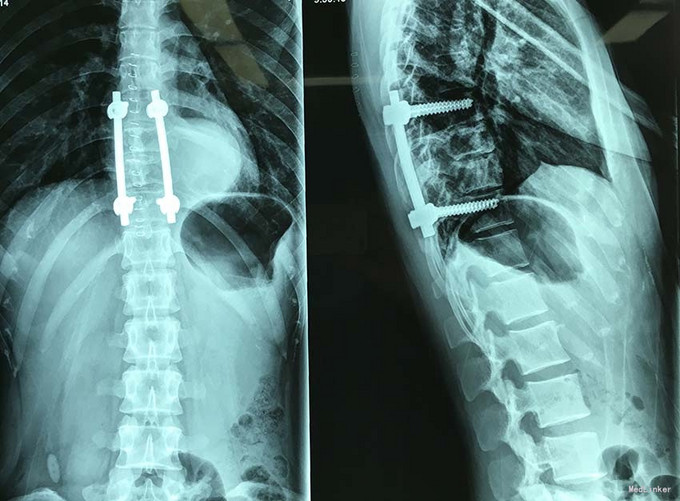

查体:脊柱外观无明显畸形,颈椎活动度正常,胸背部可见纵向长约15cm切口,皮肤钉缝合,伤口愈合可,无红肿渗液。胸椎9-10体左侧棘突旁局部压痛(+)、叩击痛(-),压头试验阴性,双侧侧臂丛牵拉实验(-),双上肢肌张力、运动、感觉及反射无明显异常、躯体感觉无明显减退,双下肢髂腰肌、股四头肌、胫前肌肌力IV级,感觉正常,双下肢直腿抬高试验(-),双侧腱反射对称略活跃,双侧Hoffman征(-),双侧Babinski征(-),双侧髌阵挛(-),踝阵挛(-)。 辅助检查:2015-11外院胸椎MRI检查发现T9-10节段椎体肿瘤并椎旁软组织肿块形成,肿块突入胸腔占位

诊断:胸椎椎体肿瘤(T9-10) 治疗:先于外院行1期后路椎弓根钉固定融合手术,然后转入我院行介入下术前椎体节段血管栓塞手术,第二天行经左侧胸腔入路椎体肿瘤病灶刮除并钛网植骨植入重建手术。术后恢复满意。复查MRI显示肿瘤病灶基本完全切除。